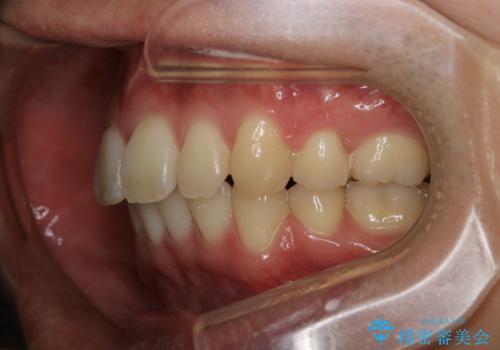

がたつき、口ゴボ(出っ歯)、真ん中のずれを抜歯矯正治療で治す。ワイヤー矯正治療

もともとの歯の根っこの位置の関係で、治療途中において上下の真ん中の位置がずれてしまいました。機能的には問題ありませんが患者様と相談し、期間を延ばした上で真ん中を合わせる治療を追加で行いました。

- 3年

- 88万円費用は治療当時の料金となります